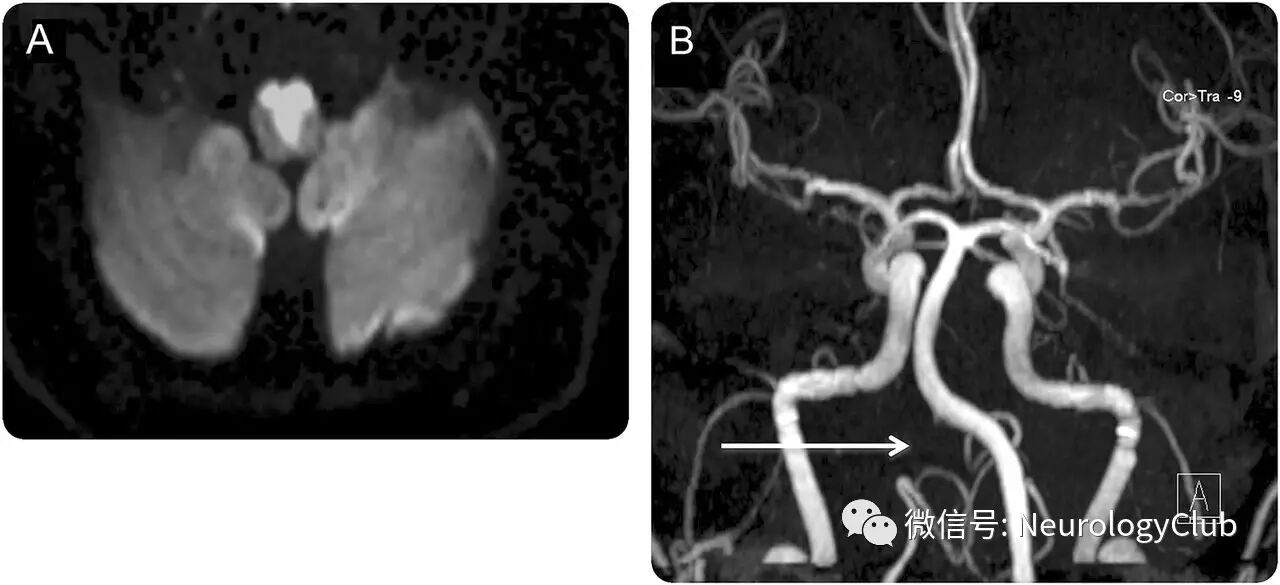

63岁有多种血管危险因素的男性,表现为突发左侧偏瘫,迅速进展至四肢瘫痪,构音障碍,双侧舌下神经麻痹和呼吸衰竭。给予重组组织型纤溶酶原激活剂静脉溶栓。MRI证实双侧延髓内侧面梗死(图,A),CT和MRA提示右侧椎动脉V4闭塞,推测可能与动脉粥样硬化相关(图,B)。3月后舌头运动完全恢复。

Dejerine综合征是一种罕见的卒中综合征;其嘴部双侧受累在MRI上呈现特征性的“心征”(图,A)。

(图:A:DWI:双侧延髓内侧面梗死;B:MRA:右侧V4闭塞[白箭])